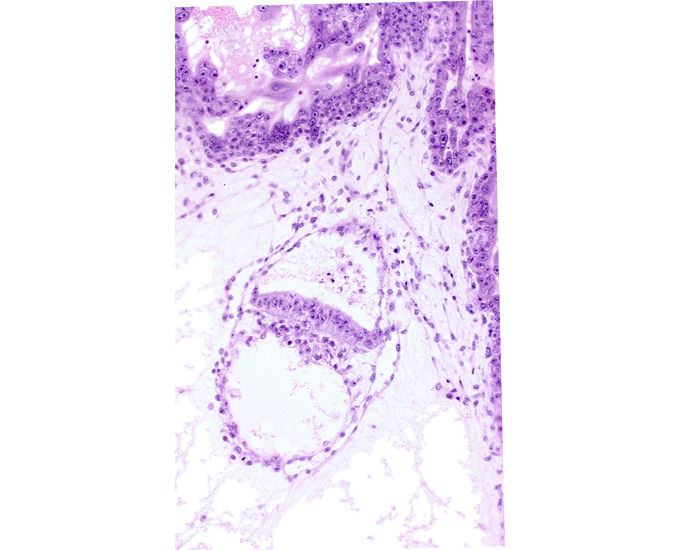

Carnegie Embryo #7801 | Location: 12-03-03

Keywords: amniotic cavity, epiblast, hypoblast, intervillus space(s), secondary umbilical vesicle cavity, stem villus, two-layered amnion

Keywords: amniotic cavity, epiblast, hypoblast, intervillus space(s), secondary umbilical vesicle cavity, stem villus, two-layered amnion